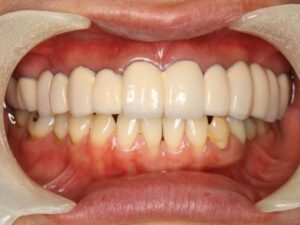

治療後の笑顔はとても自然な口元になりました。

8歯欠損14歯分のテレスコープ義歯治療 2,440,000円

全治療期間12ヶ月

治療後の経過は8年